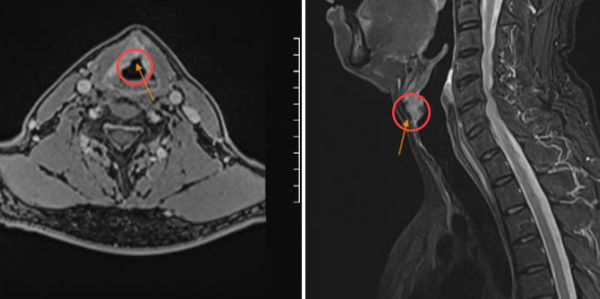

Ông Sang, một giáo viên, đã phải đối mặt với nguy cơ mất giọng vĩnh viễn sau khi được chẩn đoán ung thư thanh quản giai đoạn cuối. Suốt 9 tháng, ông Sang bị khàn giọng và mất giọng, ban đầu nghĩ rằng do đặc thù công việc phải nói nhiều nên chủ quan tự…